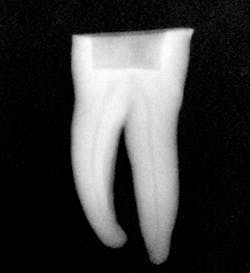

Figures 4 and 5: Clinical pre- and postoperative radiographs using the Tango techniques described.

I then use the Tango finishing instrument (double blue band on the latch head) in the same manner as described above. Always use the instrument wet. If you cannot achieve length, repeat the use of the Tango shaping instrument or use a 30/.04 SafeSider instrument to go to measurement. Confirm the Tango finishing instrument reaches the apical measurement. Move the instrument continuously against the canal walls until there is no resistance. I then fit the Tango-Endo gutta-percha point (figure 3). Figures 4 and 5 demonstrate the pre- and postop clinical radiograph.

The result is a final shape that reflects the original canal anatomy without excessive mesiodistal tooth structure removal and inadequate removal of buccolingual tooth structure.